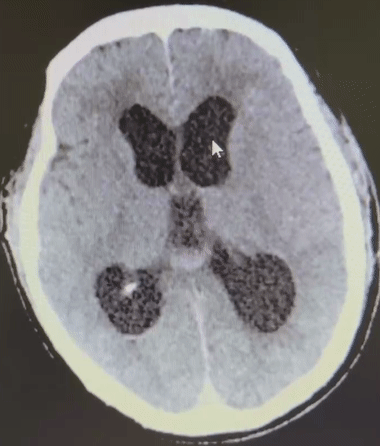

为尽快缓解患者梗阻性脑积水并颅内压增高脑疝危象情况,待麻醉平稳后,神经外科团队为患者先进行了脑室外引流(EVD),逐步释放脑脊液,梯度降低颅内压后再改侧俯“公园椅卧位”,进行显微镜下后颅窝小脑血肿清除。血肿清除后,医生在显微镜下发现患者右侧小脑海绵状血管畸形,与血肿来源位置一致,于是一并切除病变。手术顺利结束,患者术后意识障碍恢复,GCS评分达到14分,目前正在积极护理与康复中。

术后CT